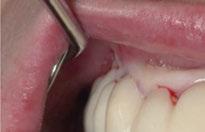

2. Exploración de tejidos blandos

El paciente presentaba biotipo periodontal grueso, con márgenes asimétricos, con recesiones gingivales a nivel de 11 y 13 y pérdida de tejidos blandos interproximales.